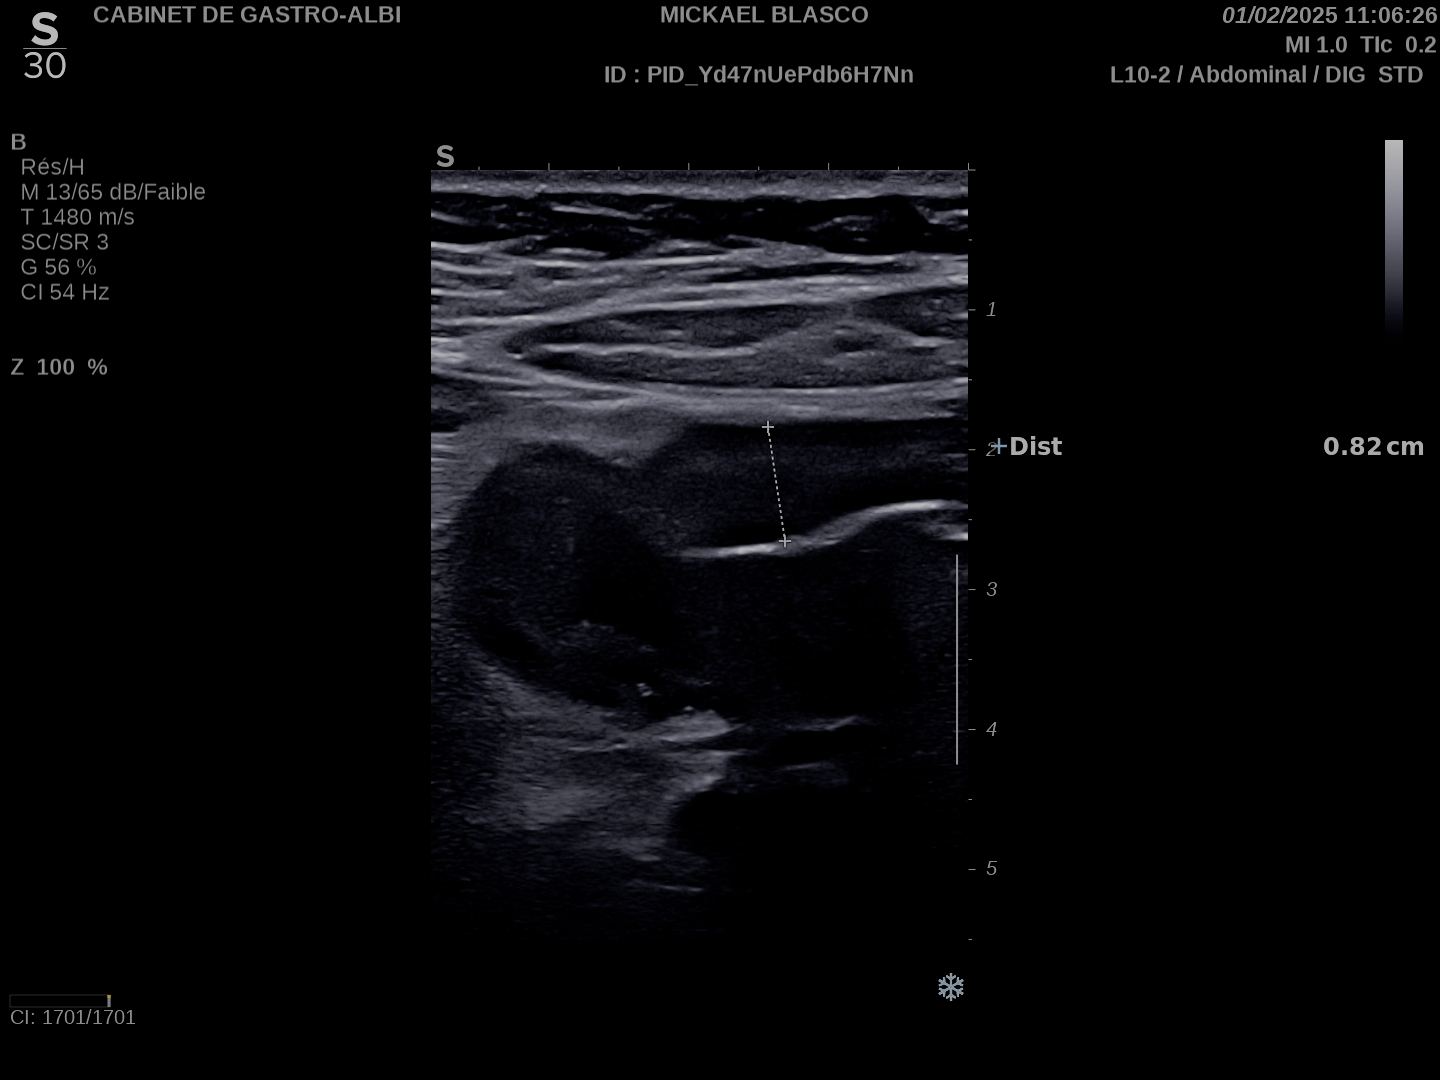

Patiente revue 4 ans plus tard sous vedolizumab Entiyo® en rémission clinique complète, biologie et calprotectine fécale normales, l’échographie (mauvaise échogénicité de la patiente) montre une paroi normalisée entre 1,8 et 2,8 mm d’épaisseur structure en couche conservée.

Le score de Milan MUC est à 3.92 confirmant la rémission échographique